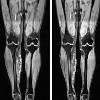

МРТ мягких тканей конечности

Члены МРТ мягких тканей. Современный высокоточный метод исследования, при котором сканирование тканей в условиях сильного магнитного поля проводится с использованием или без использования контрастного вещества. Используется на этапе уточнения диагноза, дифференциальной диагностики или тактики хирургического вмешательства. Обеспечивает детальную визуализацию мышц, связок, сухожилий, кровеносных сосудов и подкожного жира. Он проводится для определения характера, распространенности и тяжести патологического процесса при первичных и метастатических опухолях, пороках развития, травматических повреждениях (разрывы и растяжения связок, ушибы, ушибы ), Посттравматических деформаций, сдавления кровеносных сосудов и различные виды.